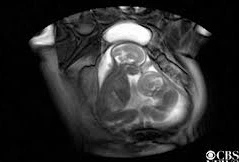

Video Video trẻ sinh đôi đá nhau giành chỗ trong bụng mẹ Các nhà nghiên cứu đã quay được một đoạn video thú vị về hai em bé tranh giành nhau chỗ trong bụng mẹ để duỗi chân thoải mái.